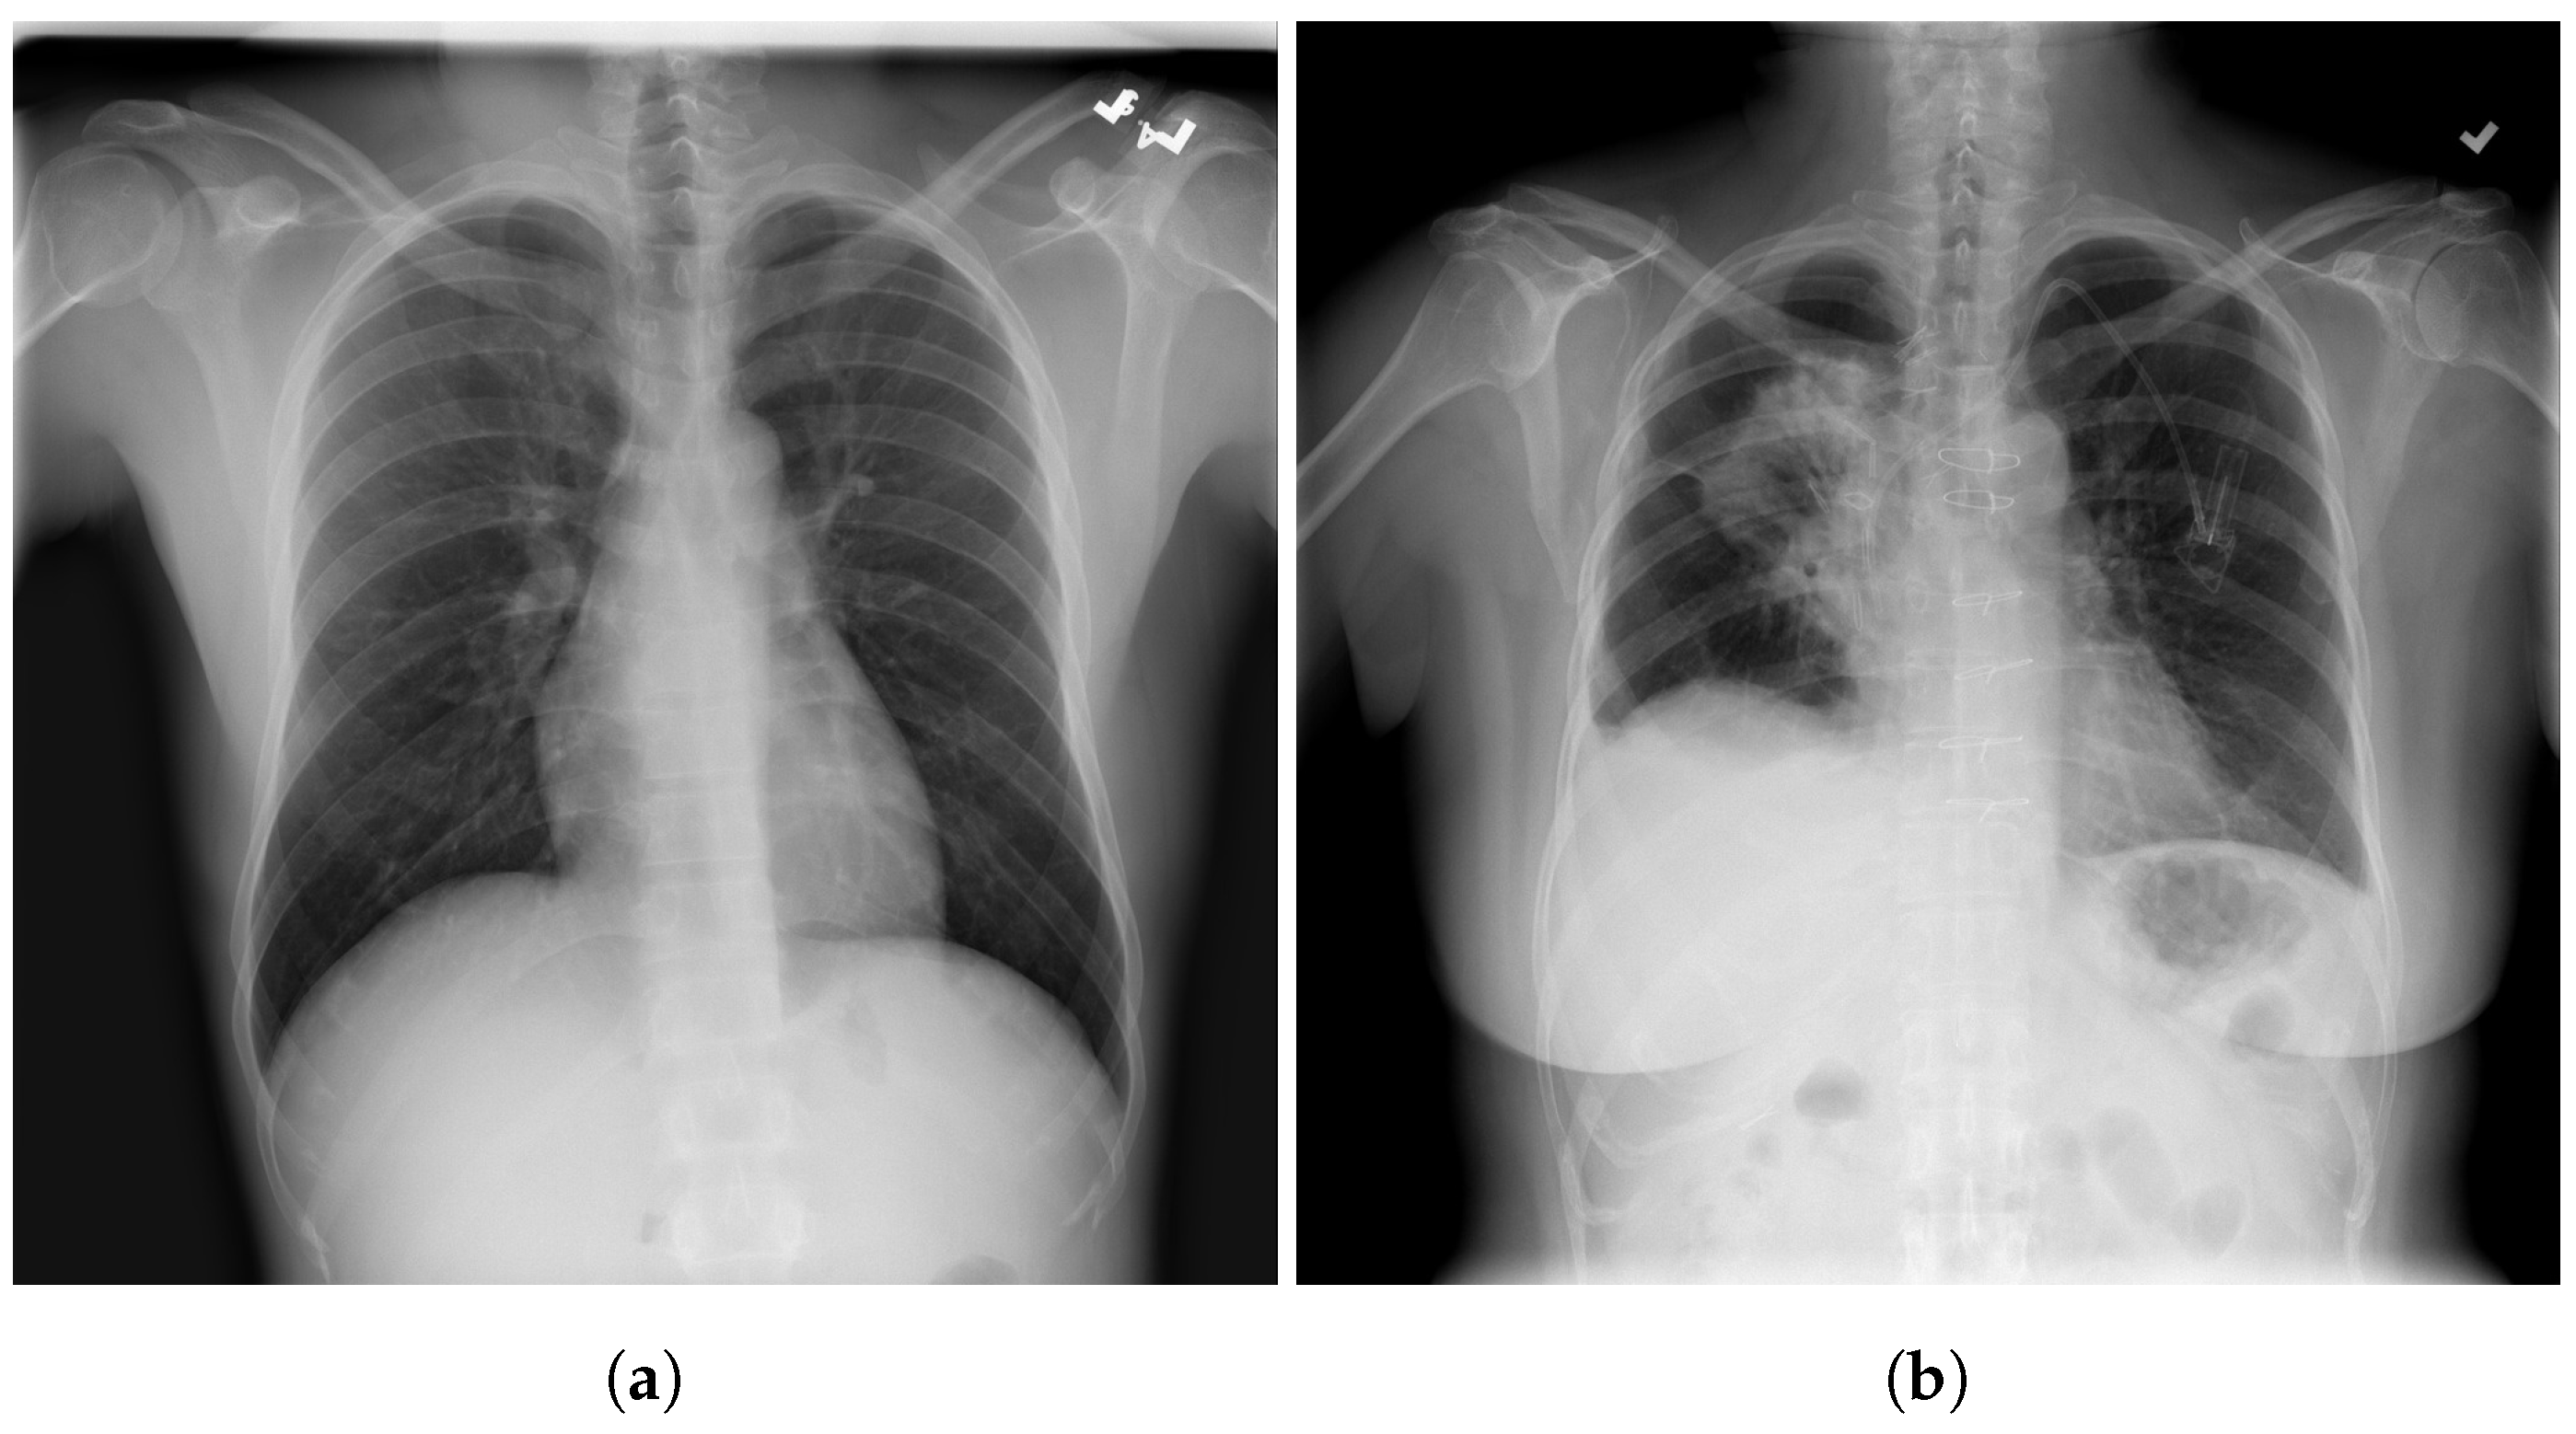

3.9. Montfort Dataset

4.1. Data Distribution for Multi-Class and Binary Models

5. Individual Tests

5.1. DeepCCXR-Bin for Individual Datasets